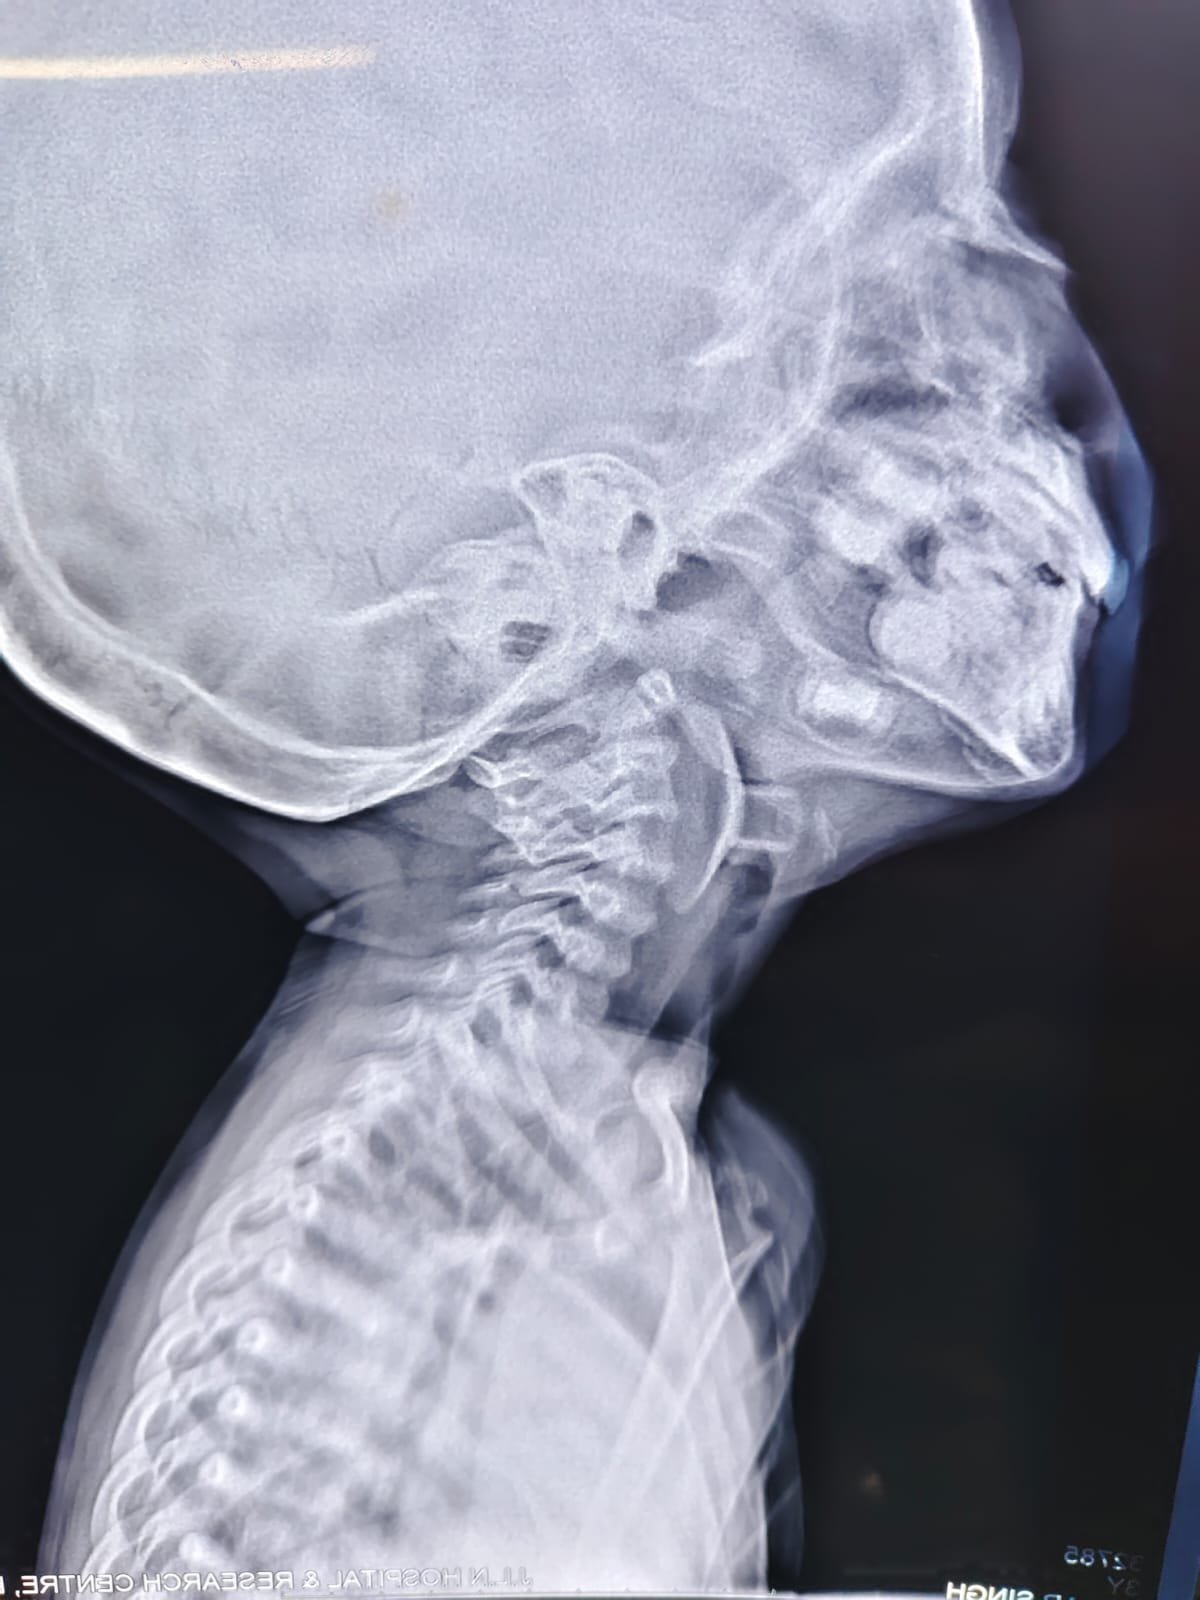

आपातकालीन विभाग में जांच के बाद पता चला कि बच्चे के श्वसन मार्ग में एक सक्शन कप एरोहेड टिप (जो आमतौर पर तीर-कमान सेट खिलौने का हिस्सा होती है) फंसी हुई थी। यह वस्तु बच्चे की जान के लिए सीधा खतरा बन चुकी थी। बिना देर किये उसे पीडियाट्रिक आईसीयू में भर्ती कर स्थिर किया गया और ईएनटी आपातकालीन ऑपरेशन थियेटर ले जाया गया।